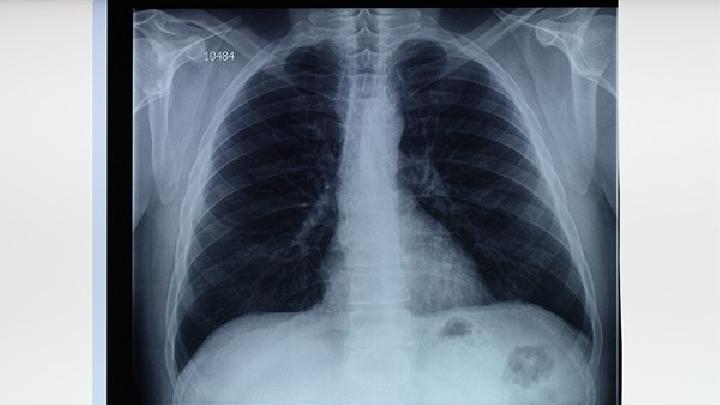

1、持续低热:无症状肺结核患者可能出现体温轻度升高,通常在37.5°C左右,且持续时间较长。这种低热可能是免疫系统对抗结核杆菌的反应。建议定期监测体温,若发现异常,及时就医进行结核菌素皮肤试验或胸部X线检查。

6、轻微咳嗽:虽然没有明显咳痰或血痰,但长期存在的轻微咳嗽可能是肺结核的早期信号。咳嗽可能与肺部炎症或结核病灶刺激有关。建议进行胸部影像学检查以排除结核感染。

无症状肺结核的早期发现至关重要,不仅能提高治疗效果,还能减少传播风险。若出现上述征兆,尤其是多种症状并存时,应及时就医进行详细检查,如痰培养、影像学检查或结核菌素试验。治疗方面,遵循规范使用抗结核药物,如异烟肼、利福平等,同时注意营养补充和适度运动,增强免疫力。定期复查,确保病情得到有效控制。